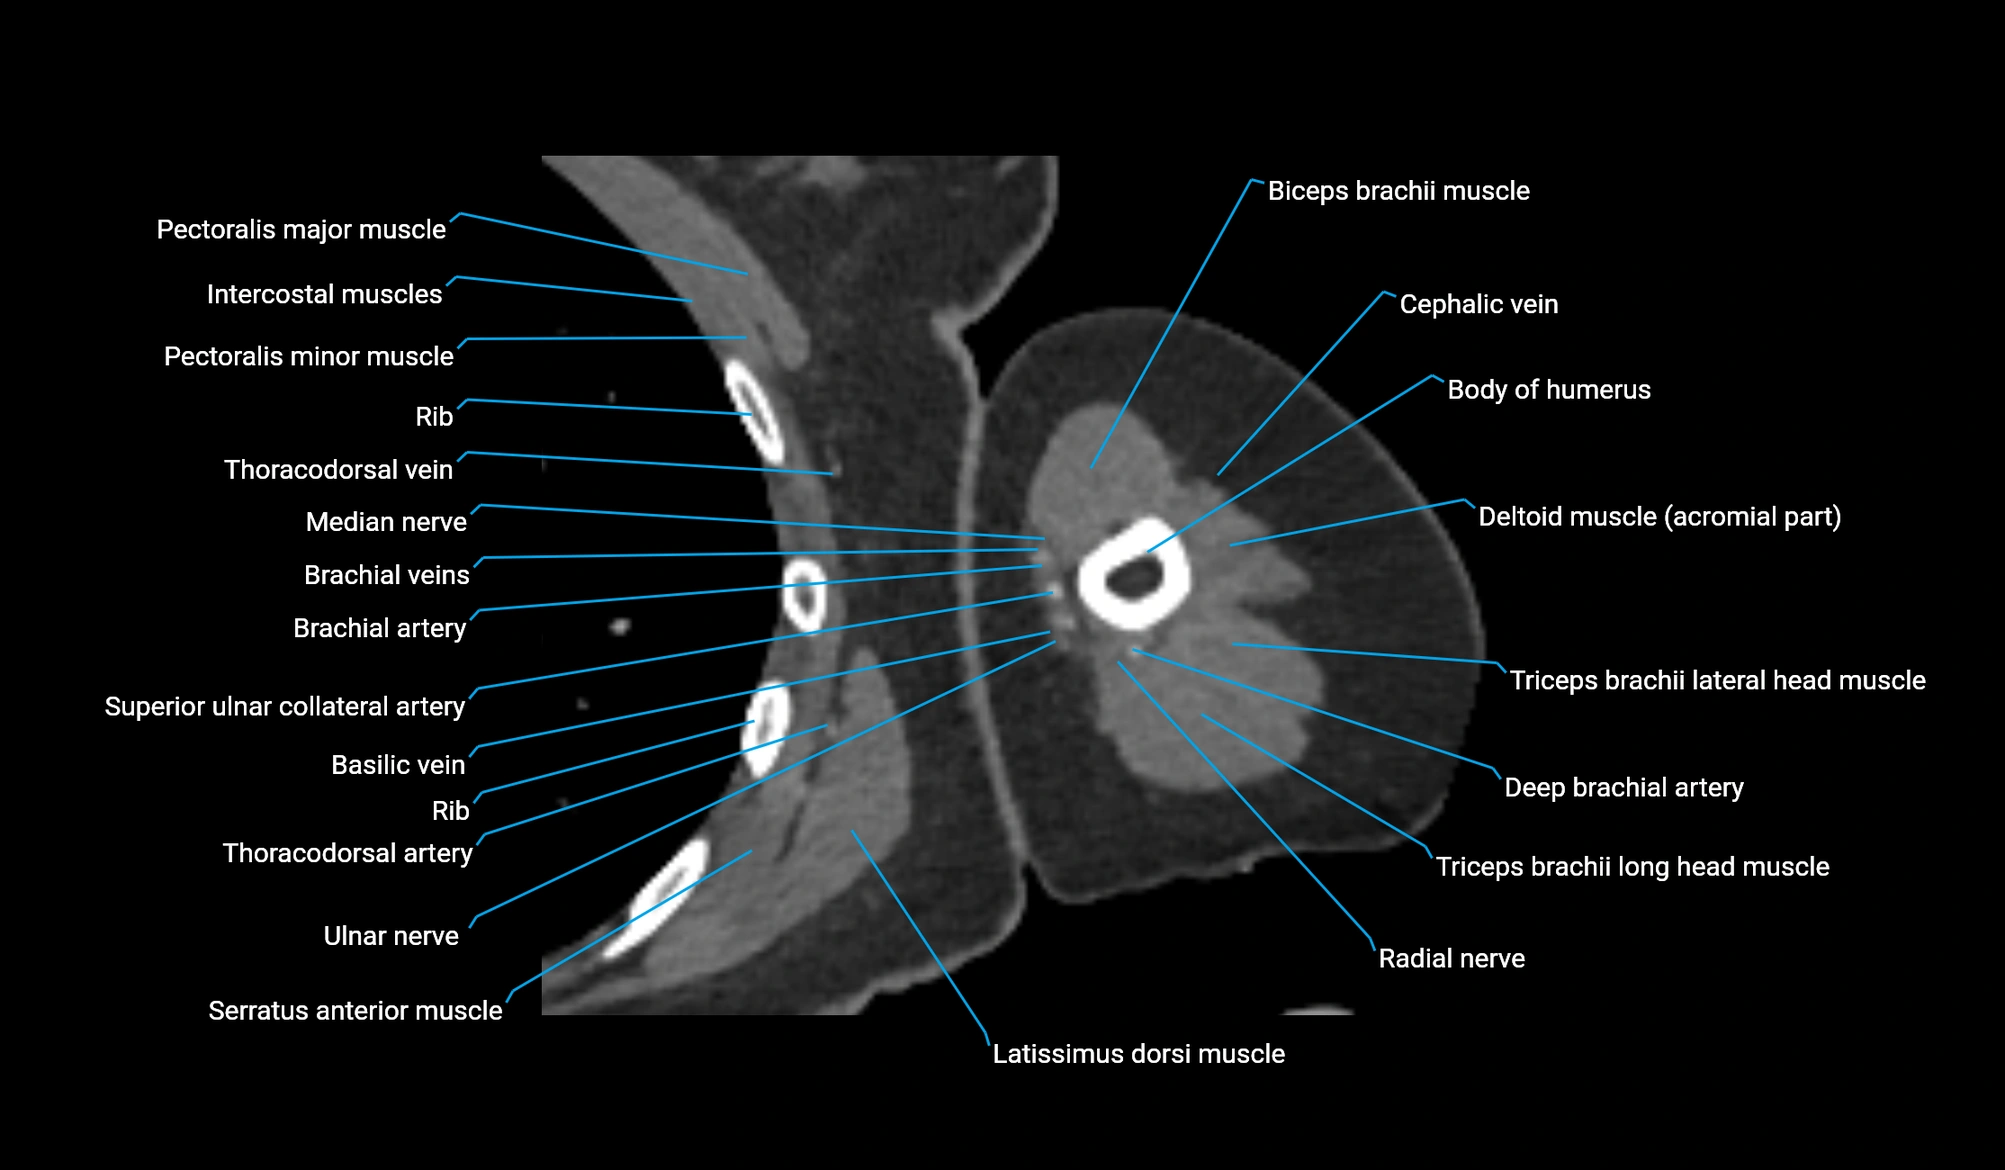

- Basilic vein

- Brachial artery

- Cephalic vein

- Deep brachial artery

- Lateral head of triceps brachii muscle

- Long head of triceps brachii muscle

- Median nerve

- Pectoralis major muscle

- Pectoralis minor muscle

- Radial nerve

- Superior ulnar collateral artery

- Thoracodorsal artery

- Triceps brachii muscle

- Ulnar nerve